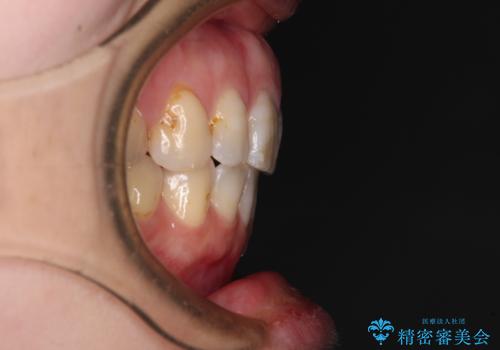

- 口元の閉じにくさと、前歯のでこぼこの歯並びを気にして来院された患者様です。

口元を積極的に引っ込めるために、上下左右の小臼歯計4本を抜歯することとしました。

セオリーでは第一小臼歯を抜歯しますが、上下右側は第二小臼歯に銀歯が装着されているため、第二小臼歯を抜歯することとしました。

上下正中を左右対称に揃えるため、アンカースクリューや補助装置を使用しながら口元を下げていくこととしました。